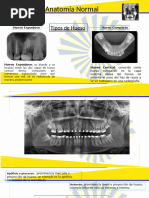

Trazado y localización de estructuras anatómicas en la radiografía

Panorámica.

 El septum presenta, en forma típica, en su porción cartilaginosa a la altura del

cornete medio, un engrosamiento llamado tubérculo septal anterior.

 Los senos maxilares se proyectan en la parte superior de los dientes y al igual que

los maxilares, se encuentran distorsionados.

 El proceso cigomático lo observamos como una estructura radiopaca en forma

de "U", "J", o "y"

 El hueso cigomático se extiende posteriormente desde el proceso cigomático del

maxilar hasta articularse con el hueso cigomático del temporal, formando el

arco cigomático.

 Apófisis mastoides Podemos ubicarlo por detrás de los tejidos blando de la oreja

 Orbitas bóveda radio lucida localizada encima de los senos nasales

 Canal infraorbitario Debido a la dirección del haz de rayos x, el conducto

infraorbitario se observa como una banda radiolucida corticada superpuesta sobre

el borde inferior de la orbita.

 La fosa pterigomaxilar se presenta como una imagen radiolucida con forma de

lagrima invertida, posterior al maxilar.

 Conducto auditivo externo Lo observamos radiolúcido de forma redondeada y

ovalada e inmediatamente por detrás del cóndilo de la mandibula.

 La apófisis estiloides del hueso temporal aparece como una proyección en la

superficie inferior del hueso temporal.

 La rama de la mandíbula, el cóndilo mandibular y la apófisis coronoides se

observan en una radiografía panorámica, aunque algo distorsionados.

 El conducto dentario inferior, al igual que en una radiografia intraoral, aparece

como una banda radiolucida dirigida en sentido anterior e inferior, y donde su

borde superior o techo no siempre se observa.

 El agujero mentoniano emerge en la superficie vestibular de la mandibula en una

dirección posterior y superior.

 El hueso hioides consta de un cuerpo con un cuero mayor y un cuerno menor.

 El término piso de las fosas nasales es usado para la línea radiopaca que

representa la unión del piso de las fosas nasales con la pared lateral de la misma.